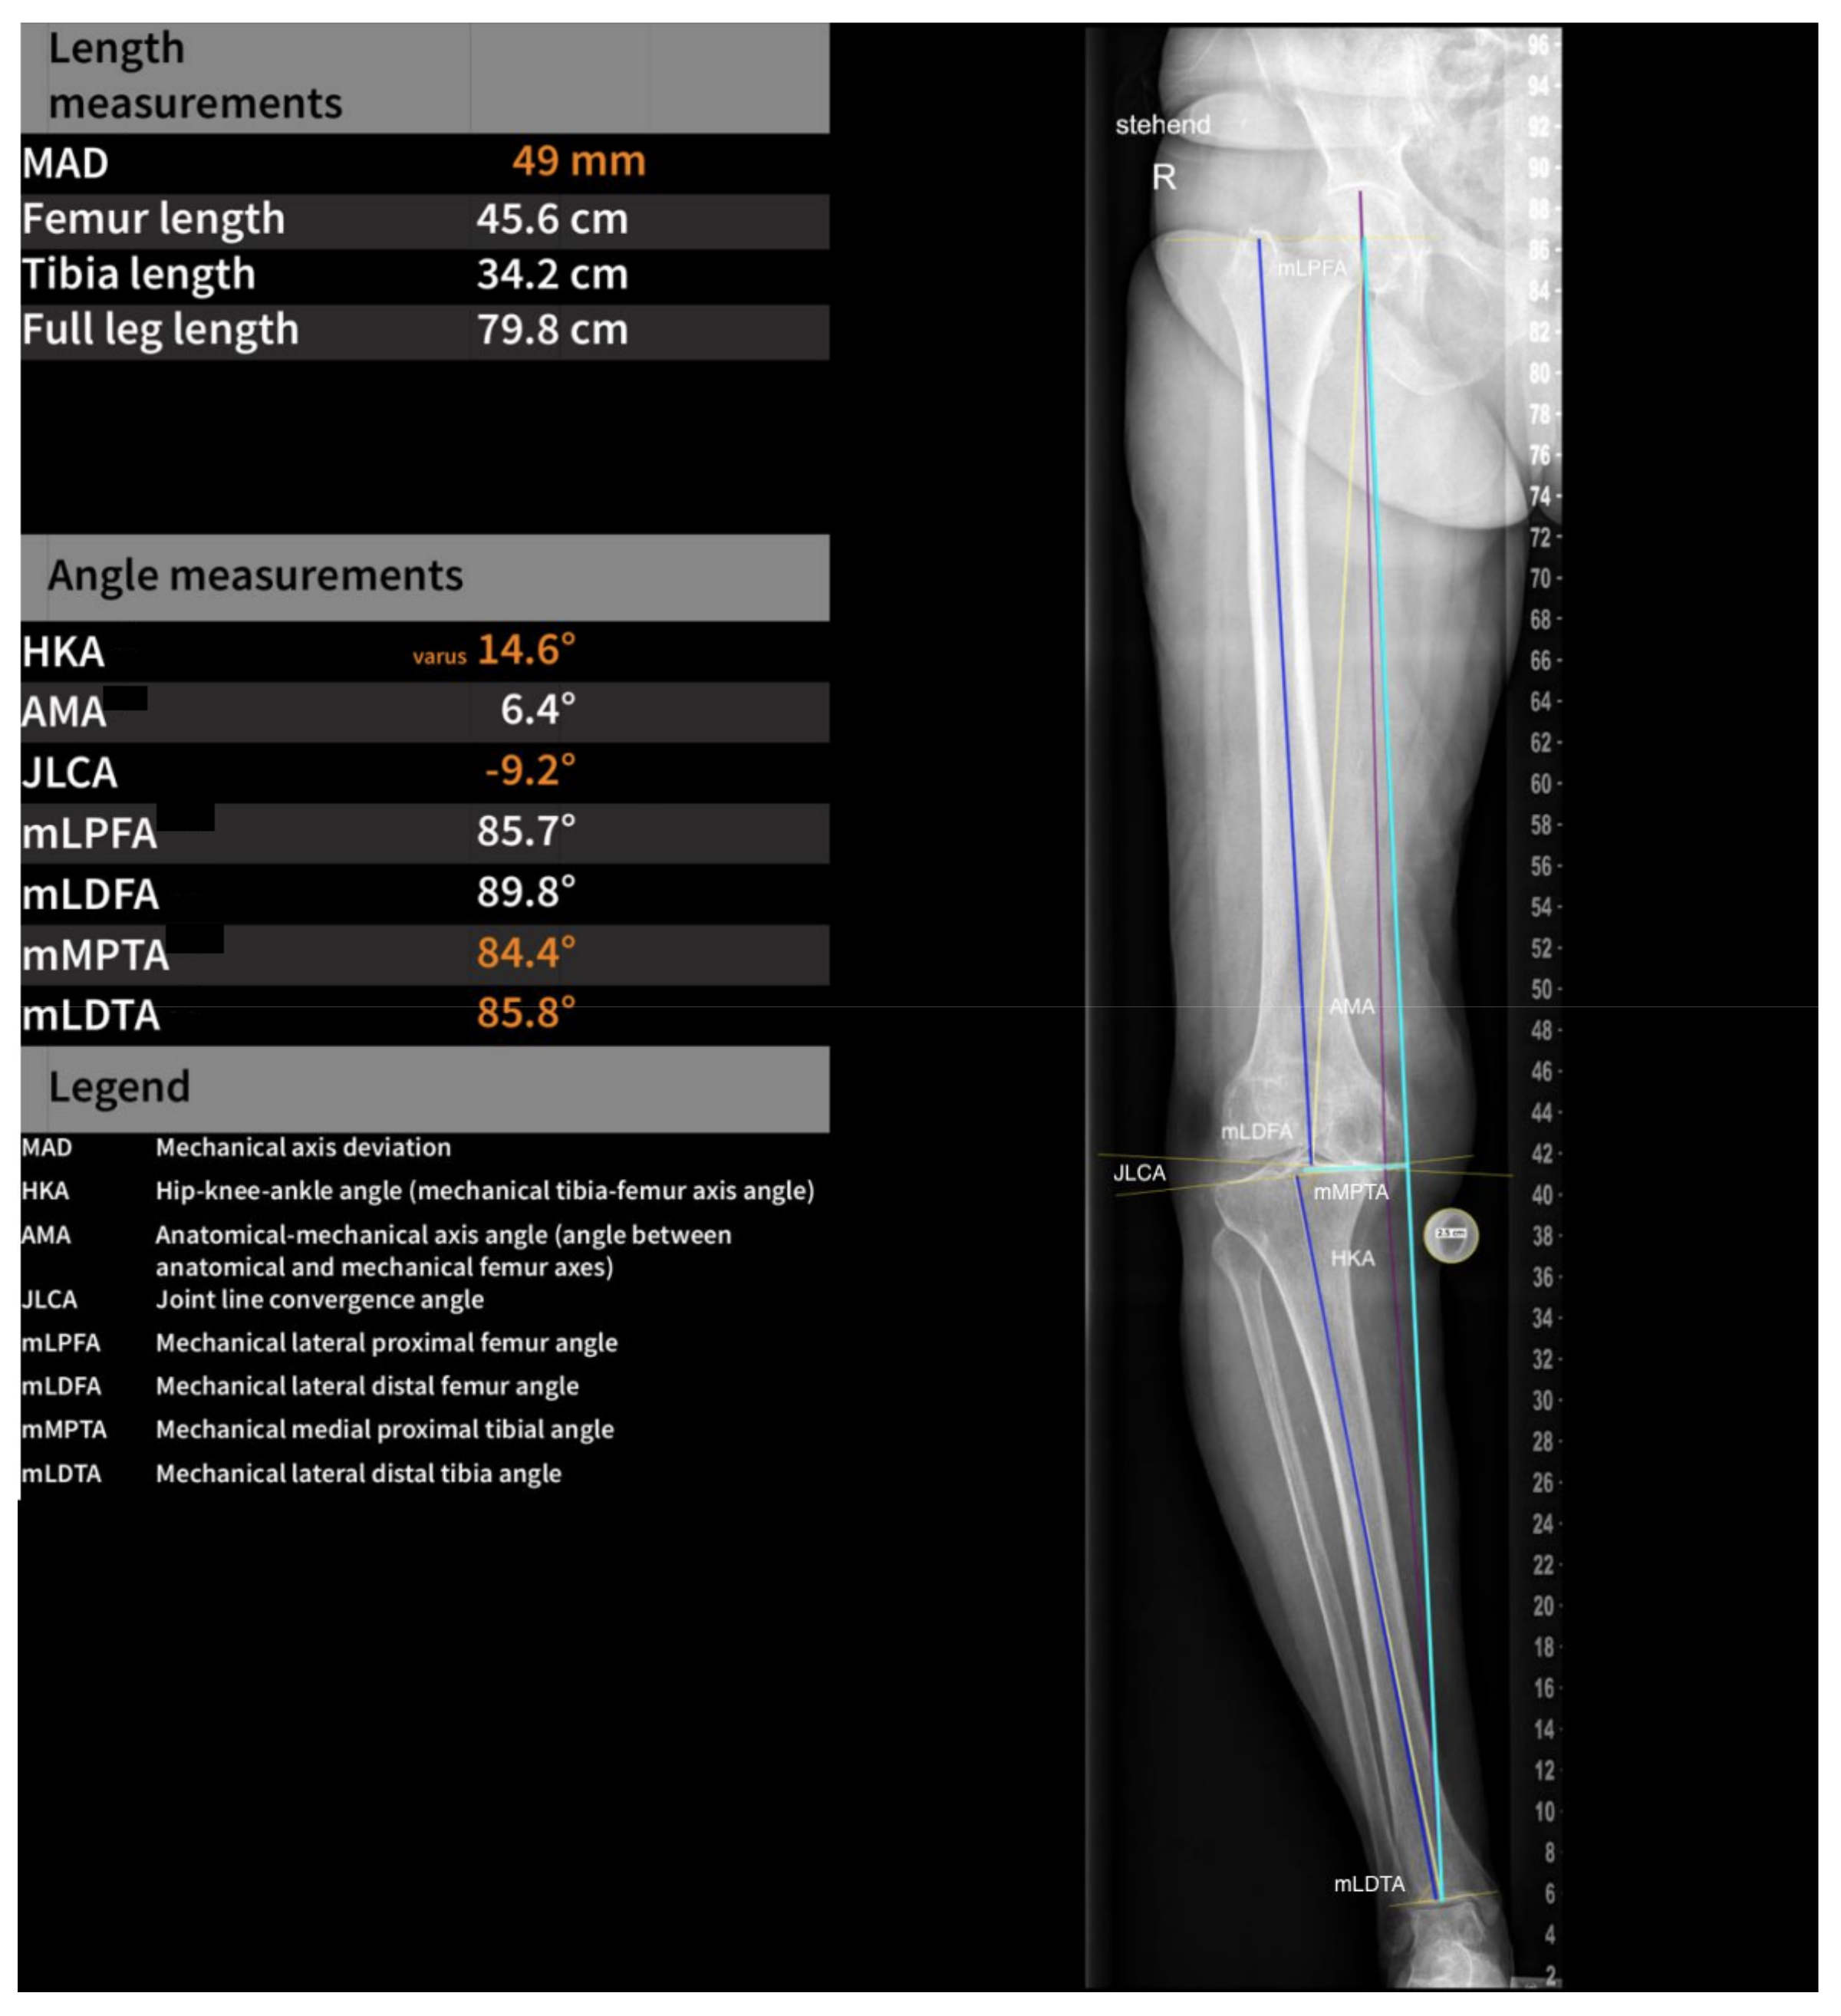

2.2. Software Measurements